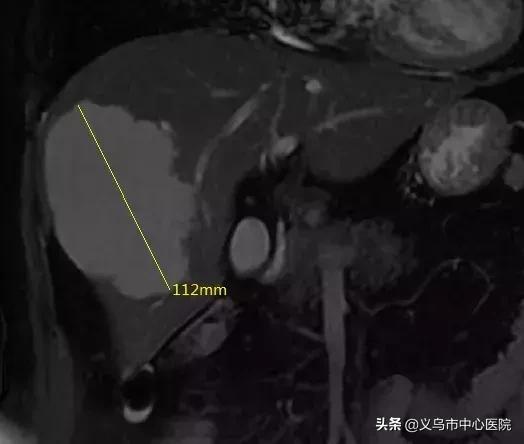

▲ 肿瘤大小112mm

2年来,祝大姐多次因哮喘引发肺部感染住院治疗,与此同时,右肝血管瘤从原来的5CM大小迅速增大至10CM多。“中心医院有浙大一院派驻的专家团队,医疗水平和服务我也非常信赖,我想搏一搏。”8月中旬,祝大姐抱着一线希望,来到中心医院院长胡振华教授坐诊的肝胆胰外科门诊。